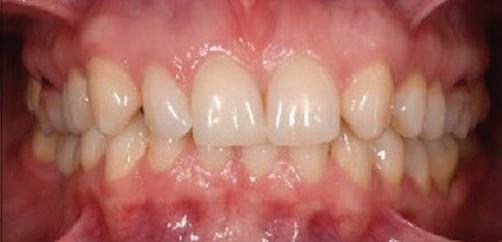

Пациентът постъпи в клиниката с молба за тотална рехабилитация на усмивката. Той не харесваше централ ните си резци, които според него бяха твърде къси и квадратни. Имаше раз стояние от медиално и дистално на латералните му резци. Друго сериоз но оплакване бе свързано с металоке рамичната корона на зъб 12, която бе жълтеникава и неестетична, като цяло не харесваше вида на венците си и както самият той се изразяваше, „вижда се прекалено много от венците при усмивка“.

Една седмица след препарацията на зъбите и циментирането на цирко ниевото кепе бяха изработени 12 IPS Empress Cad Multi фасети. Макро- и микротекстурата на фасе тите бяха направени на ръка, след кое то бяха нанесени 3D характеризации с боички, а полирането отново бе напра вено ръчно, за да им се придаде естест вен и естетичен вид. Предизвикателството тук беше короната да има същите оптични характеристики като тези на остана лите зъби при естествена светлина, през поляризационен и флуоресцентен филтър. 3D принтерът бе Fromlabs, софтуерът за фрезоване – Mill Box, а фрез апаратът –imes icore CORiTEC 350i. В крайна сметка постигнахме ес тествен вид на усмивката с натурал на зъбна морфология при изцяло диги тален протокол, при който дизайнът бе направен първоначално и през всич ки етапи на лечението се придържахме към него до самия край Излишно е да отбелязваме, че всички сме удовлетворени от постигнатото! Преди След Победител в категория „Клиничен случай с изцяло дигитален протокол“ в конкурса „Усмивка на годината 2022“